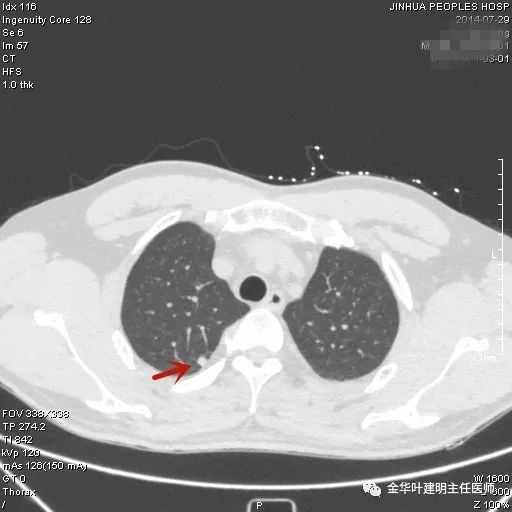

上图示典型的肺内淋巴结影像。靠近胸膜,高密度,三角形工多边形,相对比较孤立,周围没有炎性渗出或卫星灶,邻近胸膜(包括叶间胸膜)但无胸膜牵拉凹陷。